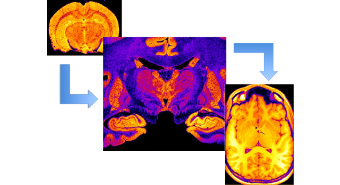

Unterstützt werden diese Aktivitäten durch die Konstruktion und Implementierung neuer Hardware. Ein weiterer Forschungsschwerpunkt ist die Kombination von MRT und Positronen-Emissions-Tomographie (PET) in einem kombinierten MR-PET Gerät. Die Kombination eröffnet einzigartige Möglichkeiten zur Erforschung und Anwendung neuer Methoden der grundlagenorientierten und translatorischen Hirnforschung.

- MR-PET